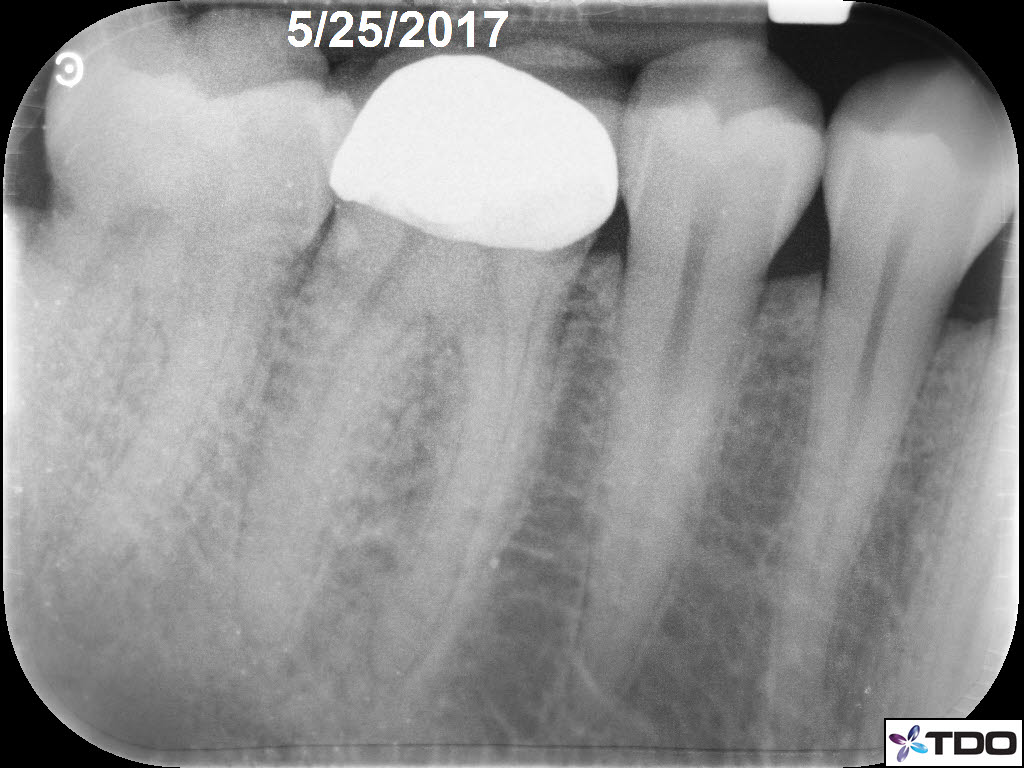

In the hierarchy of dentin conservation the existing restorative has the lowest priority and it quite frankly gets in the way of our access to the root canal system. But, after practicing directed dentin conservation for a while, you sometimes get lucky. The patient is 40yo. She was symptomatic at the time of treatment and interestingly the mesiobuccal canal was partially vital while the mesiolingual, distobuccal and distolingual canals were partially necrotic. She was asymptomatic at the completion visit as well as at the follow-up appointments.

Hi Gergely. The crown was less than two weeks old when the patient was first seen in my office. The previous crown was 15 yrs old and was seldom sensitive; the RD replaced the crown due to an “open margin.” Heat/cold sensitivity ensued after the crown prep. Four days after the permanent crown was cemented the patient woke up with severe throbbing pain and the temp sensitivity became worse. When she presented to my office she reported severe biting tenderness and tender submandibular lymph nodes.